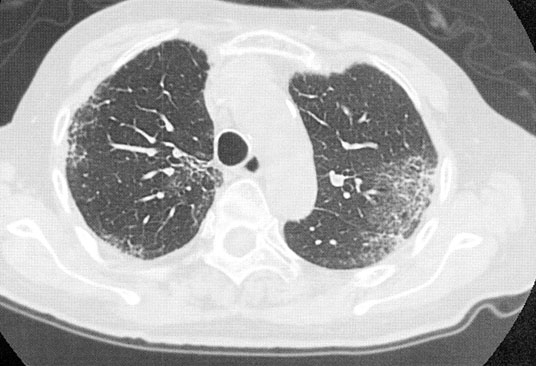

An 81-year-old woman being treated for chronic urticaria consulted our outpatient clinic with a two-week history of productive cough and fever. Six months prior to the consultation, she consulted a dermatologist and was treated with an antihistamine-1-receptor blocker against urticaria. Since her itching continued, diaminodiphenyl sulfone (DDS), 50 mg daily, was added. The chronic urticaria then gradually improved, and the DDS was continued. Two weeks prior to the consultation, she developed malaise and cough with whitish sputum. On thoracic computed tomography (CT), a bilateral upper lobe and subpleural lesion-dominant, multiple, nonsegmental, consolidative shadow was observed (Figure 1). The possibility of community-acquired pneumonia was highly suspected, and a combination of clarithromycin and ceftriaxone for one week was given at a family practice office. However, her symptoms and the infiltrative shadow on chest X-ray gradually worsened, and she consulted our outpatient clinic. On physical examination, auscultation of her chest showed early inspiratory crackles. Blood laboratory examination showed: white blood cell count 9150/μL, eosinophils 5.8% (531/μL), red blood cell count 2,800,000/μL, hemoglobin 8.8 g/dL, hematocrit 28.1%, platelet count 249,000/μL, total protein 6.8 g/dL, albumin 4.0 g/dL, AST 20 IU/mL, ALT 9 IU/mL, LDH 201 U/mL (normal range: 106–211 U/mL), Fe 76 μg/mL, ferritin 402 mg/mL, total iron-binding capacity 110 μg/mL, Na 145 mEq/L, K 4.0 mEq/L, Cl 110 mEq/L, C-reactive protein 8.3 mg/dL, CEA 1.1 ng/mL, and KL-6 197 U/mL (normal range: 0–499 U/mL). The Coombs test was negative. A bronchofiberscopic examination was also performed. Bronchoalveolar lavage (BAL) cells showed elevated eosinophils (34.1%) and total cell count (2.67 × 105/mL). The CD4/CD8-ratio of BAL cells was 3.56 (normal range: 1.0–2.0). No specific pathogen was recognized in the BAL fluid. A diagnosis of eosinophilic pneumonia was made, and the possibility of an adverse effect of DDS as the cause of eosinophilic pneumonia was suspected. Prednisolone, 25 mg daily (0.5 mg/kg/day), was then started, and DDS was discontinued immediately. Her productive cough and fever resolved, and the infiltrative shadow on chest X-ray and thoracic CT also improved gradually (Figure 2). Anemia and eosinophilia were also improved, with eosinophils of 0.2% (22/μL) and hemoglobin of 11.3 g/dL. After three months of treatment with tapering of prednisolone, the prednisolone was discontinued. Two years later, there was no recurrence of eosinophilic pneumonia.

Figure 1: Thoracic CT imaging on admission showed bilateral upper lobe and subpleural lesion-dominant, multiple, nonsegmental, consolidative shadows.